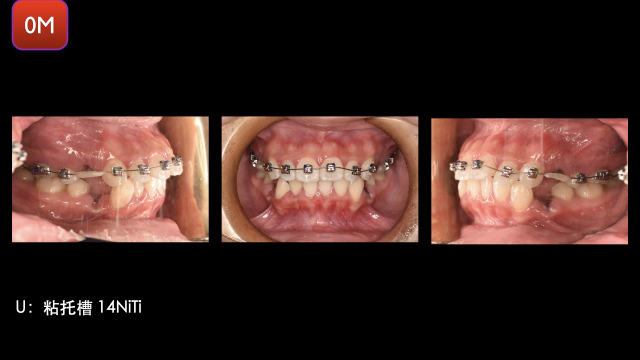

术前检查

术中治疗